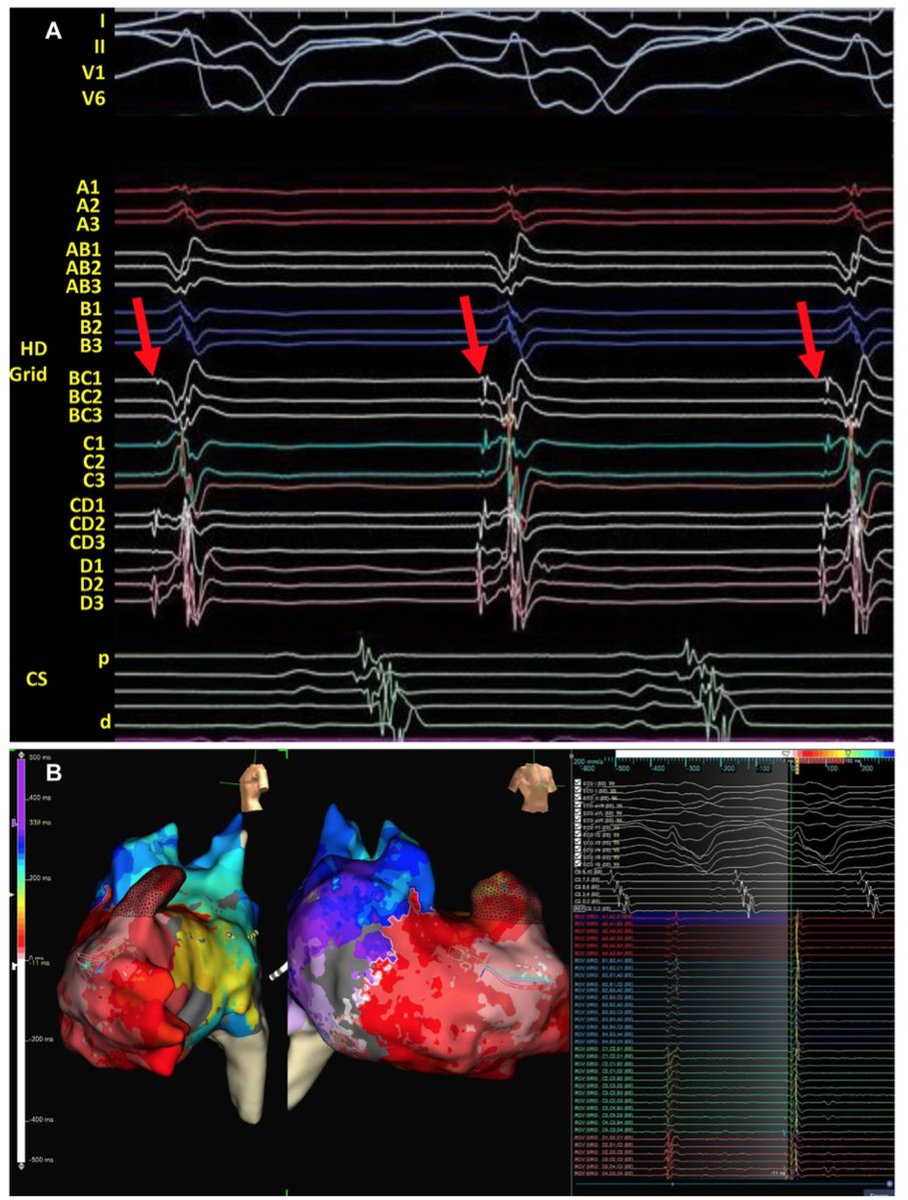

Calling all EP Fellows! Dr. Michael Bernard from @OchsnerEP will be sharing real-world case studies tomorrow night at 7:00 pm EST featuring #EnSiteOT and #TrueEGMs! REGISTER HERE: zoom.us/webinar/regist… @AbbottCardio #EPeeps